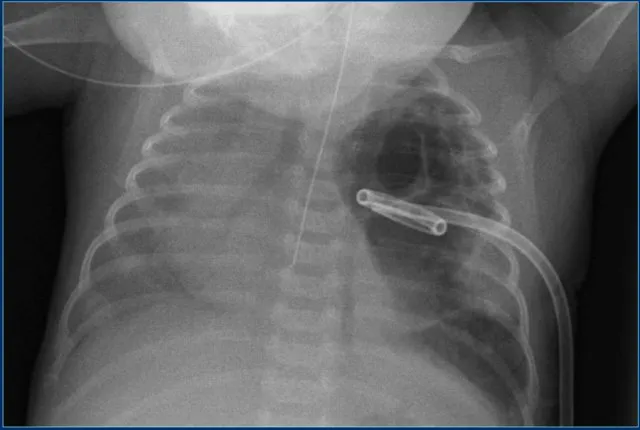

- Umbilical Venous Catheter (UVC):

- Ideal: Tip at cavo-atrial junction (T8-T9).

- Path: Umbilical v. → L portal v. → ductus venosus → IVC.

- Malpositions: Portal vein (liver damage), RA (arrhythmia).

⭐ UVC tip ideally at the junction of IVC and right atrium (T8-T9 vertebral level).

- Chest Tube (ICD):

- Pneumothorax: Apical. Effusion: Basal.

- All side holes within pleural space.